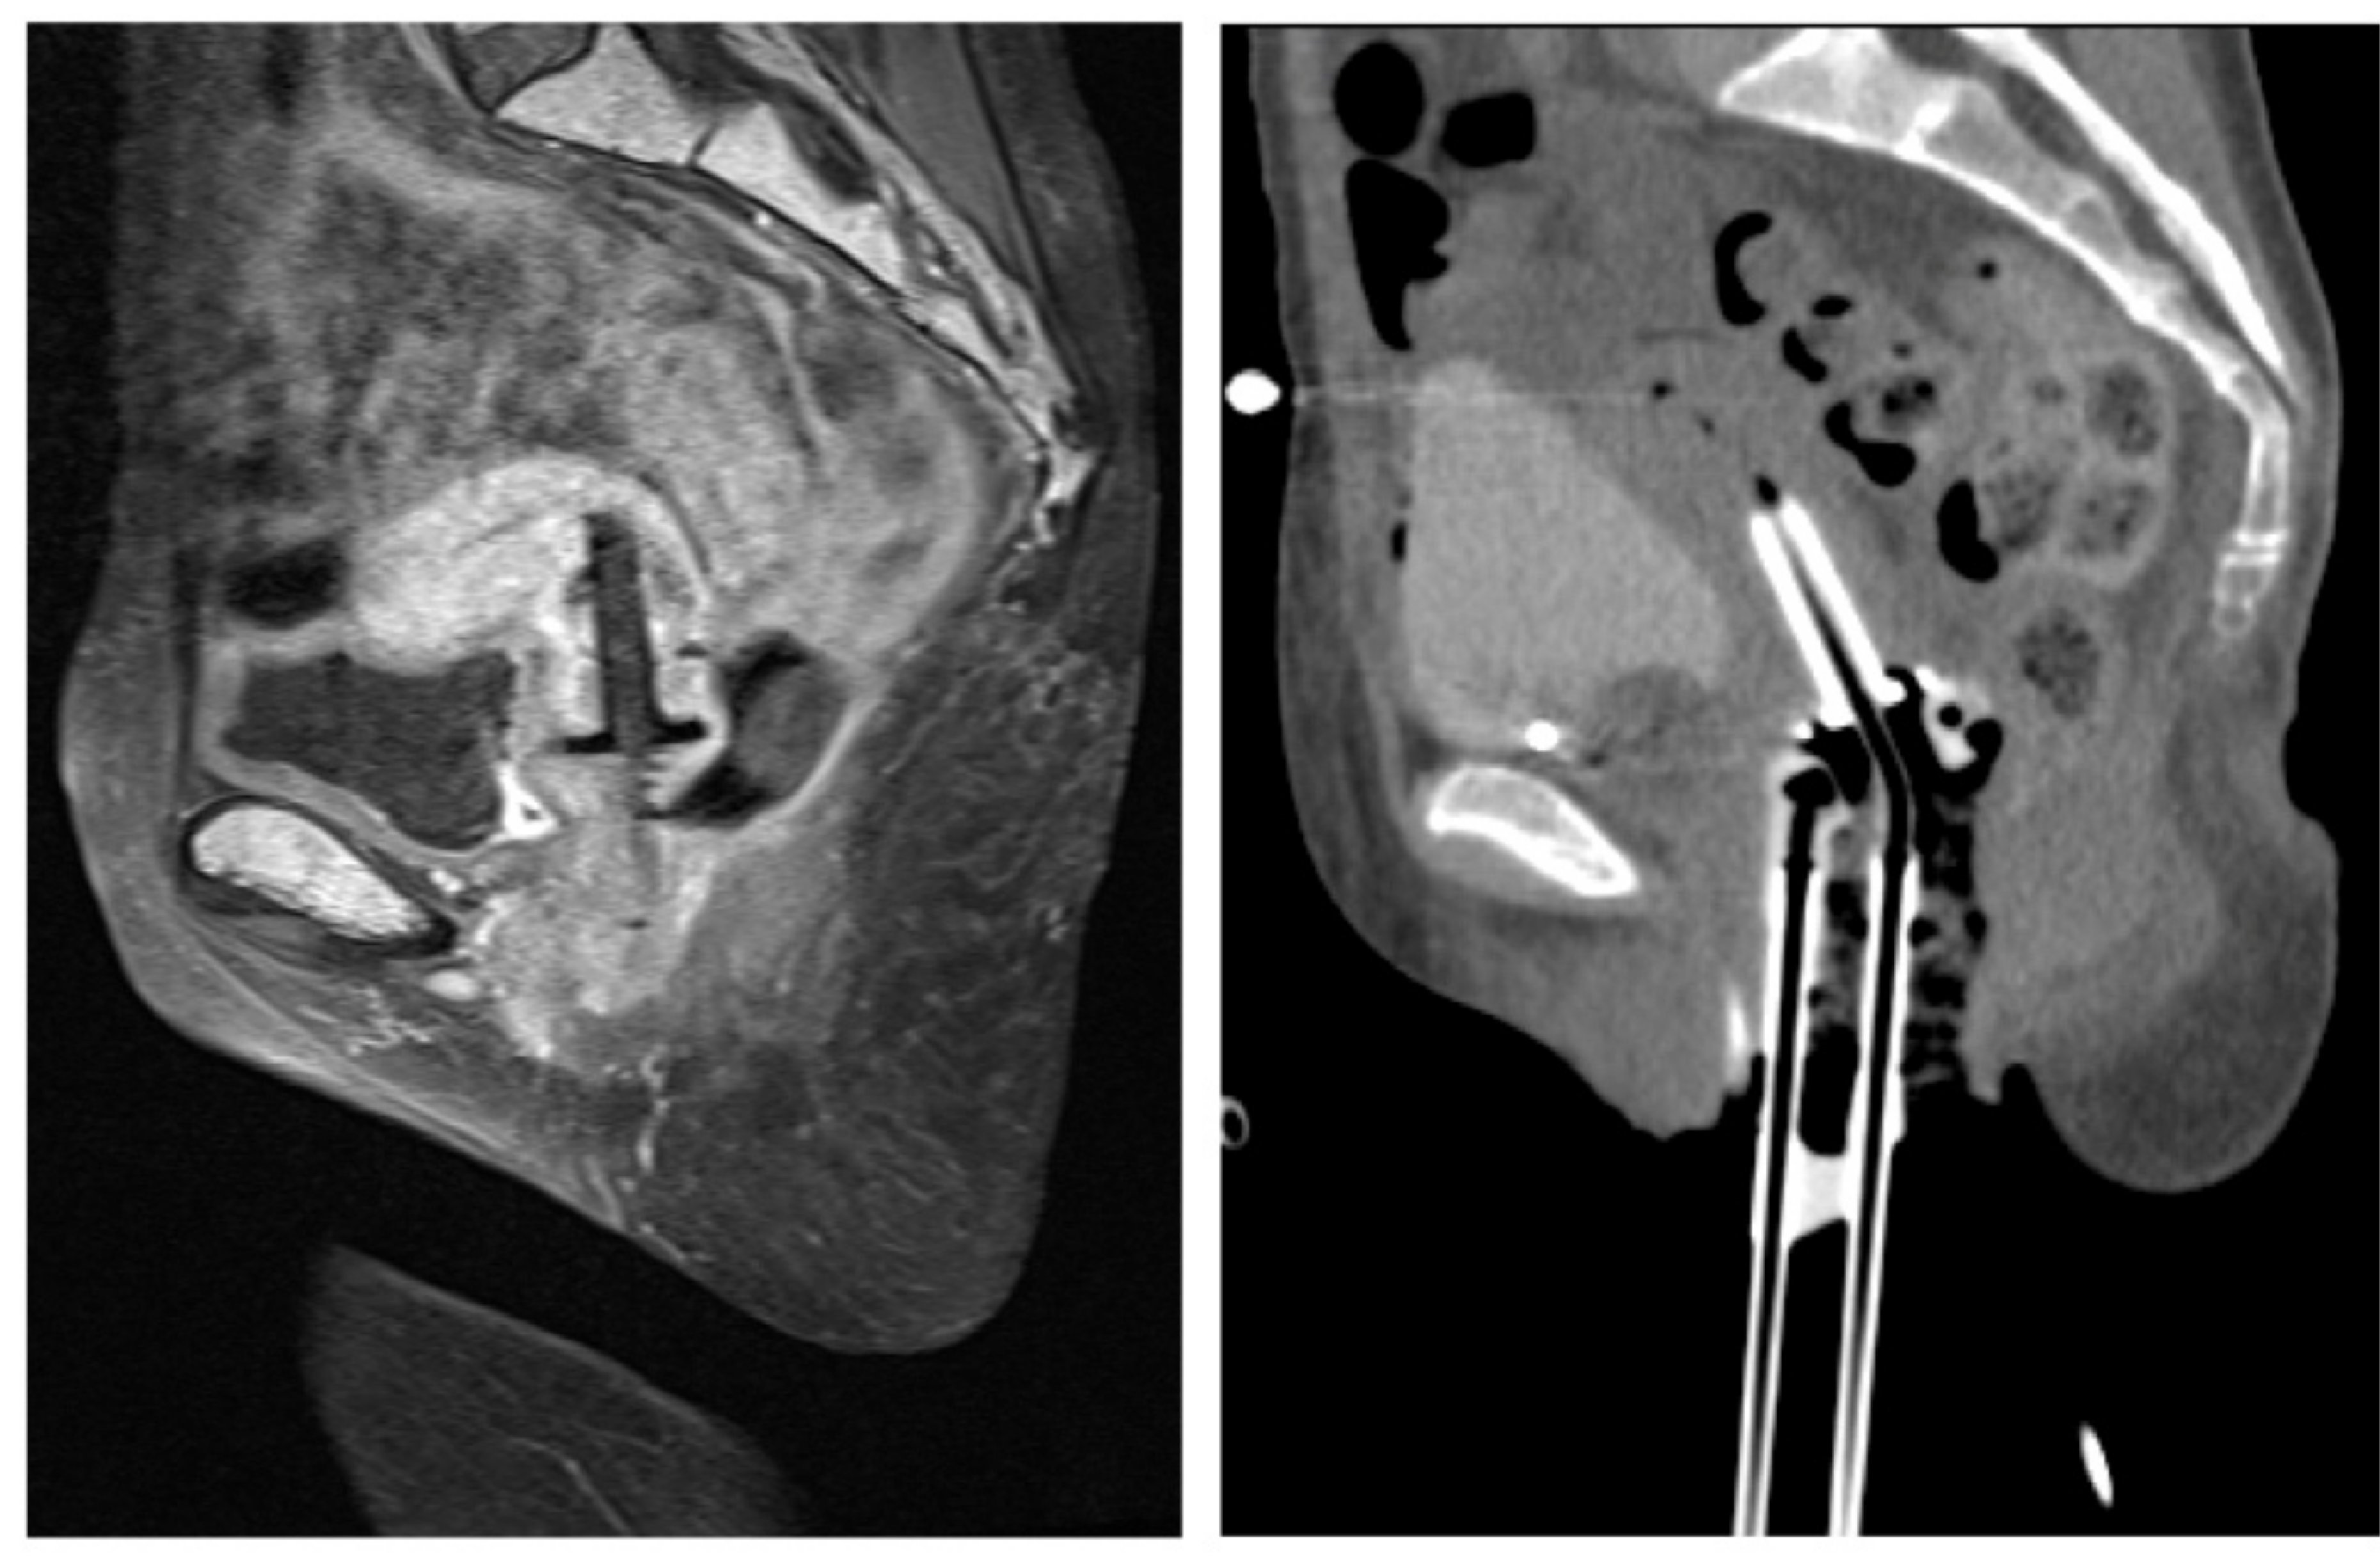

The Fusion of MRI and CT in the Planning of Brachytherapy for Cancer of the Uterine Cervix

2. Materials and Methods